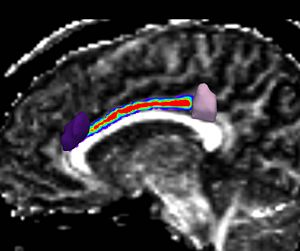

| − | [[Image:IC_sto_fig.jpg|thumb| | + | [[Image:IC_sto_fig.jpg|thumb|right|200px|Figure 4: Stochastic Tractography of the Internal Capsule]] |

:* Stochastic Tractography is also comparable, if not better, in defining large white matter fiber bundles, especially those traveling through white matter regions characterized by increased diffusion uncertainty (fiber crossings). Example of such application to internal capsule. (Figure 4) | :* Stochastic Tractography is also comparable, if not better, in defining large white matter fiber bundles, especially those traveling through white matter regions characterized by increased diffusion uncertainty (fiber crossings). Example of such application to internal capsule. (Figure 4) | ||

- Stochastic Tractography is also comparable, if not better, in defining large white matter fiber bundles, especially those traveling through white matter regions characterized by increased diffusion uncertainty (fiber crossings). Example of such application to internal capsule. (Figure 4)